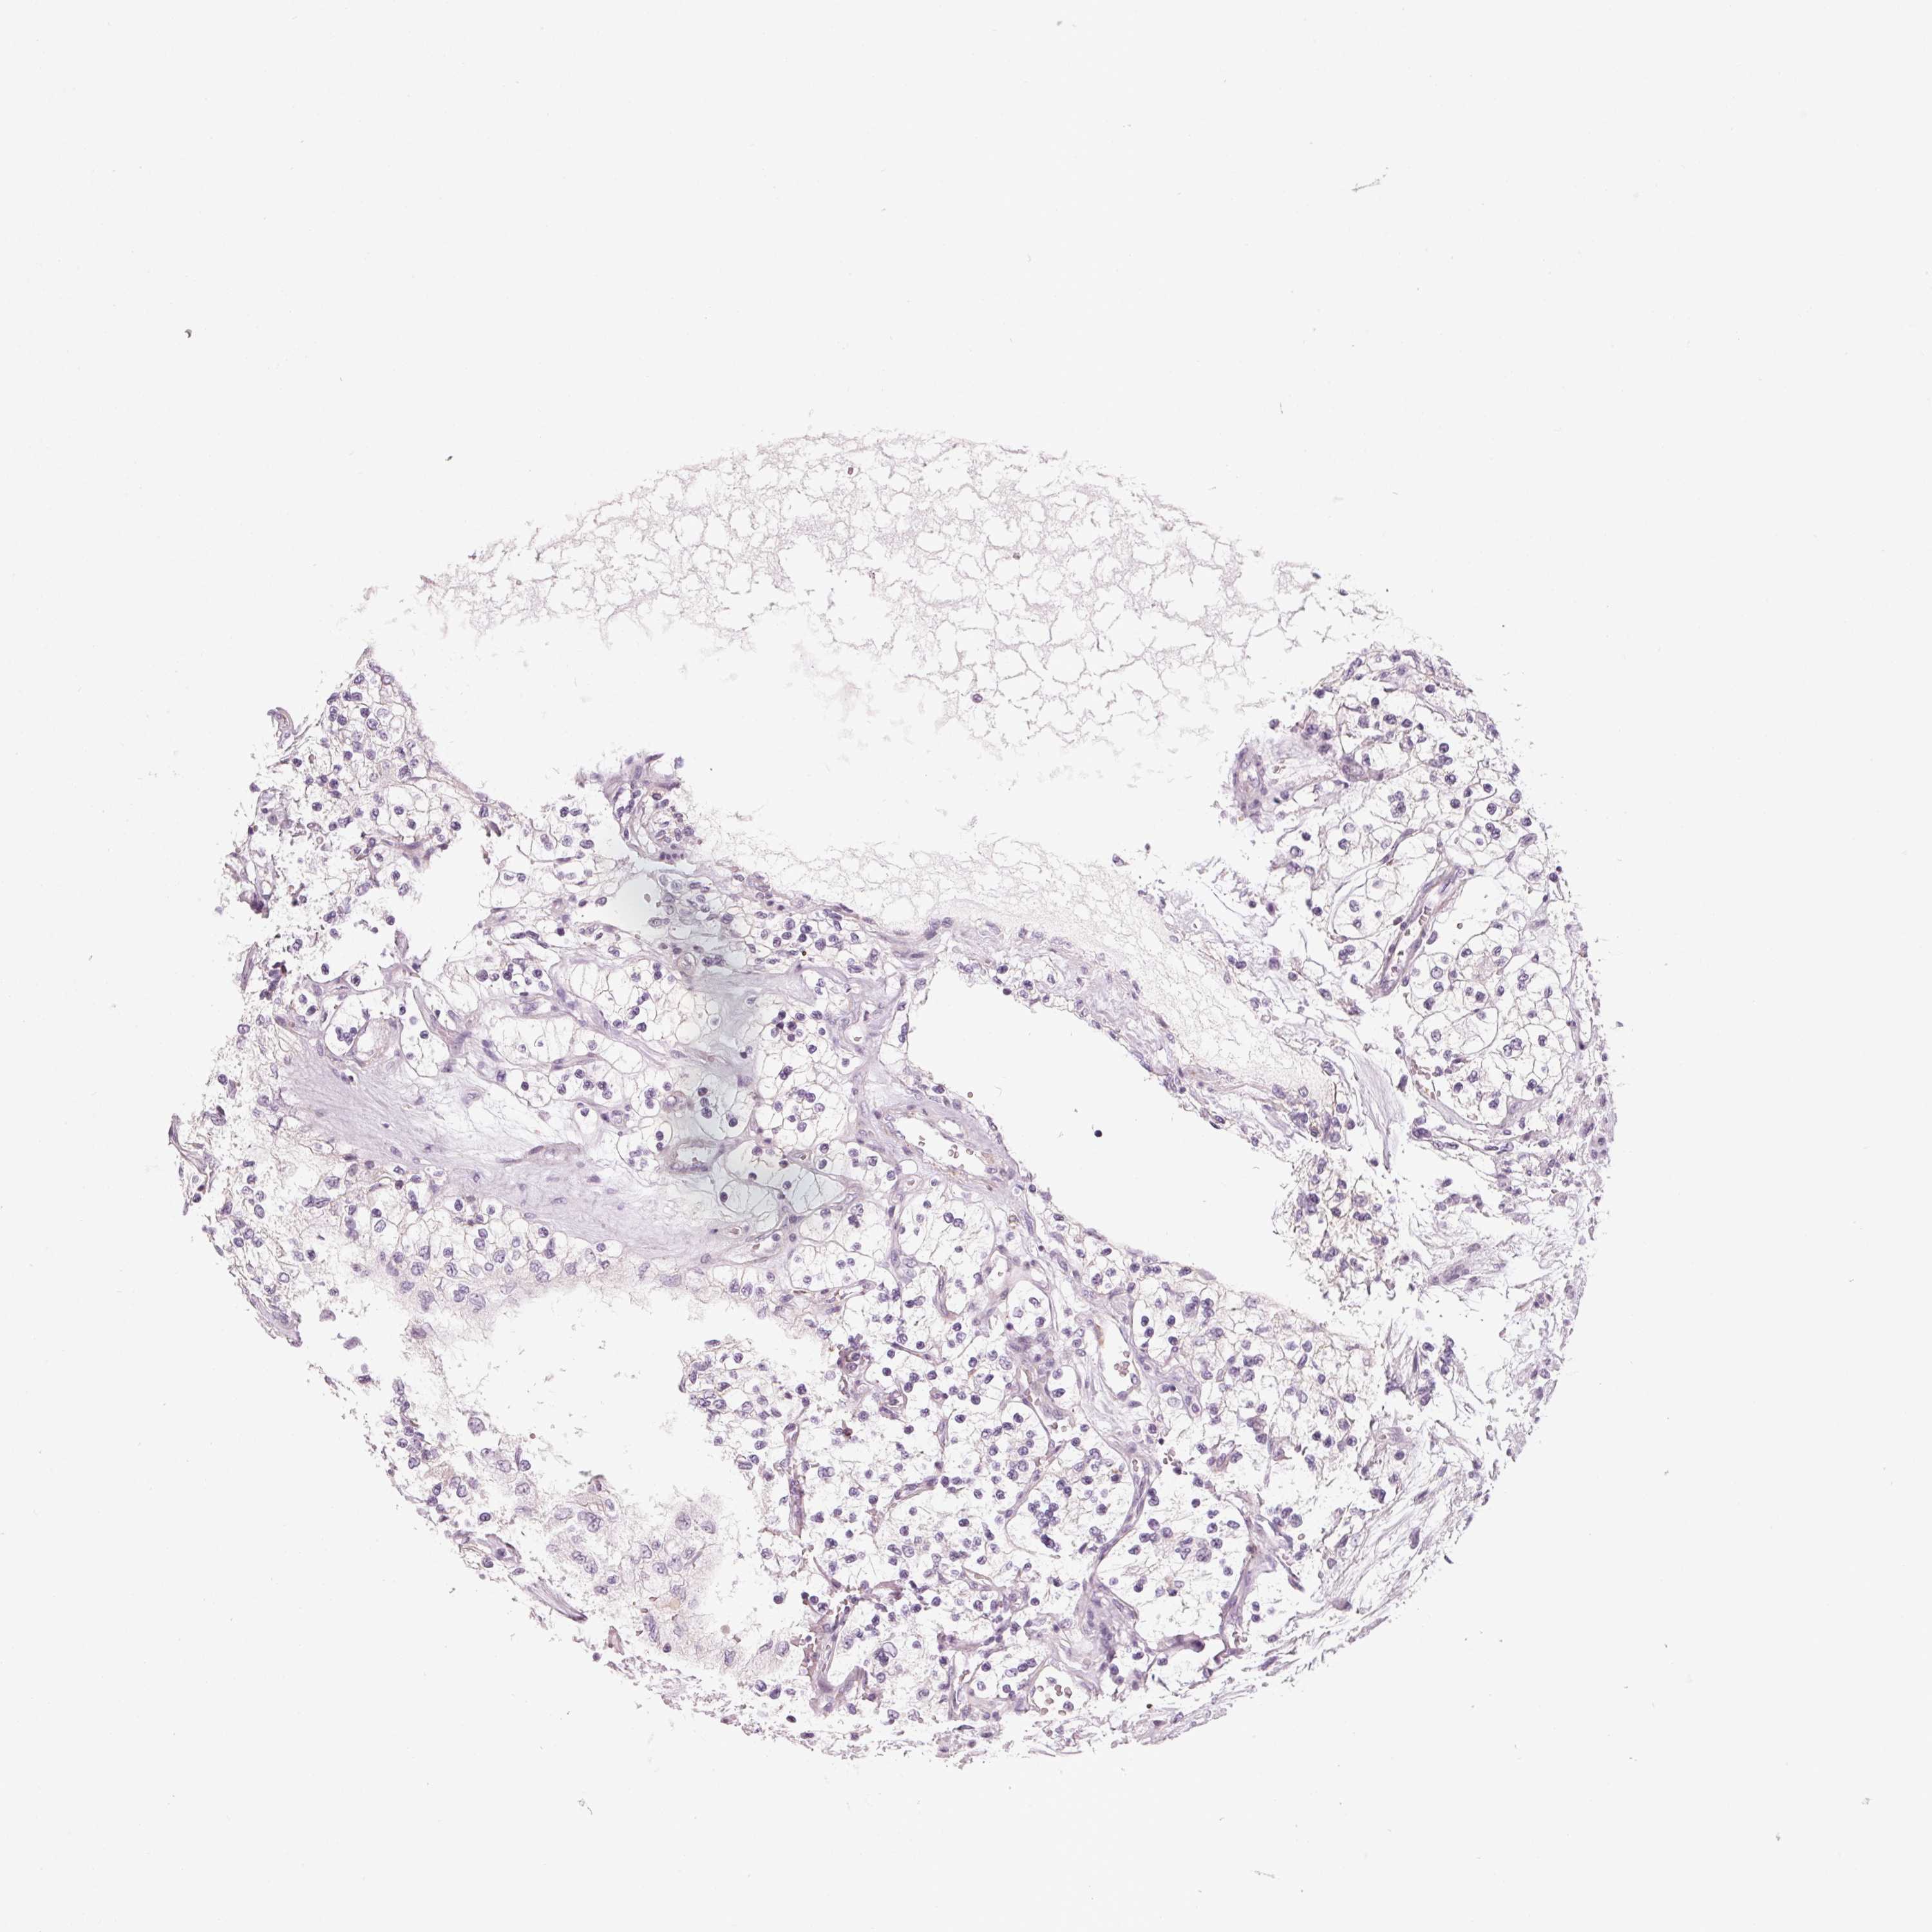

KIDNEY RENAL PAPILLARY CELL CARCINOMA (TCGA) - Interactive survival scatter ploti

The Survival Scatter plot shows the clinical status (i.e. dead or alive) for all individuals in the patient cohort, based on the same data that underlies the corresponding Kaplan-Meier plots. Patients that are alive at last time for follow-up are shown in blue and patients who have died during the study are shown in red.

The x-axis shows the expression levels (FPKM) of the investigated gene in the tumor tissue at the time of diagnosis. The y-axis shows the follow-up time after diagnosis (years). Both axes are complimented with kernel density curves demonstrating the data density over the axes. The top density plot shows the expression levels (FPKM) distribution among dead (red) and alive patients (blue). The right density plot shows the data density of the survived years of dead patients with high and low expression levels respectively, stratified using the cutoff indicated by the vertical dashed line through the Survival Scatter plot. This cutoff is automatically defined based on the FPKM cutoff that minimizes the p-score. The cutoff can be changed by dragging the vertical line or by entering a cutoff value in the square labeled "Current cut-off".

Under the Survival Scatter plot the p-score landscape (black curve; left axis) is shown together with dead median separation (red curve; right axis). Dead median separation is the difference in median mRNA expression between patients who have died with high and low expression, respectively. It is calculated as follows: median FPKM expression of dead patients with high expression - median FPKM expression of dead patients with low expression. This is intended to aid the user in visually exploring custom cutoffs and the associated p-scores and dead median separation.

Individual patient data is displayed and can be filtered by clicking on one or more of the category buttons on the top of the page. Categories describing expression level and patient information include: high, low, alive, dead, female, male and tumor stages. The scale of the x-axis can be toggled between linear and log-scale by clicking on the "x log" button. Mouse-over function shows TCGA ID, patient information and mRNA expression (FPKM) for each patient.

& Survival analysisi

Kaplan-Meier plots summarize results from analysis of correlation between mRNA expression level and patient survival. Patients were divided based on level of expression into one of the two groups "low" (under cut off) or "high" (over cut off). X-axis shows time for survival (years) and y-axis shows the probability of survival, where 1.0 corresponds to 100 percent.

ITPKA is not prognostic in Kidney Renal Papillary Cell Carcinoma (TCGA)